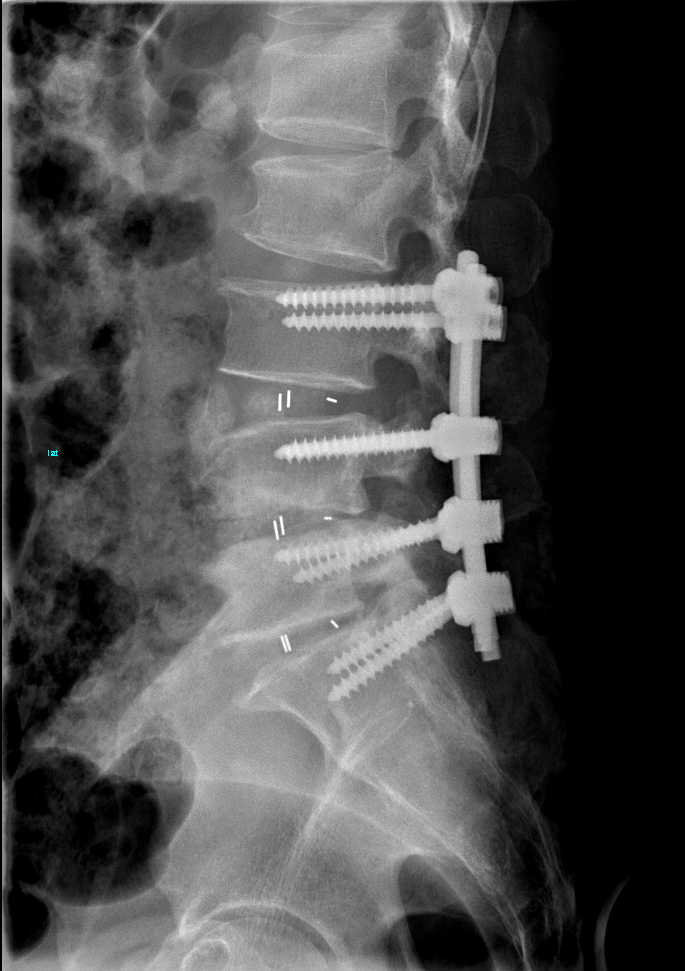

术中李清主任清除了患者椎管压迫物,扩大椎管,并用椎弓根丁棒系统固定,打开了椎管的通路,为受压迫的脊髓神经提供功能恢复的空间。

患者术后第一天就可以下地行走,会阴部麻木、双下肢麻木完全消失,大小便可以自解,一周后顺利出院。